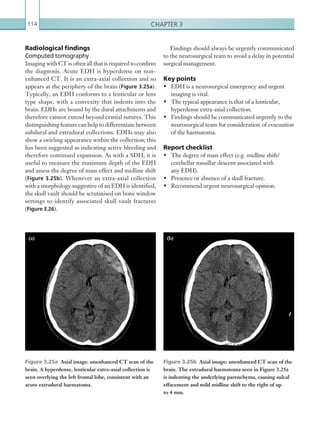

5Thoracic imaging Figure 1.3 Coronal image: IV contrast enhanced CT scan of the thorax in the arterial phase. A dissection flap can be seen extending from the aortic root and involving the brachiocephalic trunk, which may compromise distal blood flow into the right common carotid artery and right subclavian artery. Figure 1.4  Axial image: IV contrast enhanced CT scan of the thorax in the arterial phase. A dissection flap is shown within the aortic root. In addition, hyperdense material is seen in the pericardium consistent with haemopericardium (arrow). This may occur in coronary artery rupture as a result of dissection. Figures 1.2a, b  Axial images: IV contrast enhanced CT scans of the thorax in the arterial phase. There is a serpiginous, linear structure within the aortic arch containing flecks of calcification consistent with an aortic dissection flap (arrow). Figure 1.2b demonstrates the importance of appropriate window width and level, as the dissection flap is barely visible without image manipulation. (a) (b) K22247_C001.indd 5 16/05/15 3:06 AM

• 28.

Chapter 16 required. Cardiacmotion artefact, which commonly occurs in the region of the aortic root, can be misinterpreted as a dissection flap. Familiarity with this artefact can prevent a false-positive result (Figure 1.5). The dissection can also extend caudally into the descending thoracic and abdominal aorta; the coeliac axis, SMA and IMA should be closely inspected for involvement. Furthermore, it is useful to identify which of the main abdominal aortic branch vessels arise from thefalselumen,astheseareatriskofischaemia.Coeliac axisinvolvementcanresultin liver or splenic ischaemia, whichtypicallypresentsasreducedenhancement.SMA or IMA involvement can result in bowel ischaemia (see Chapter 2:Gastrointestinalandgenitourinaryimaging, Bowel ischaemia and enterocolitis). Both intramural haematoma and aortic dissection should be classified according to the Stanford or DeBakey model; this has important prognostic and management implications (Table 1.2). LOCATION MANAGEMENT Stanford A Involving thoracic aorta proximal to origin of left subclavian artery. Surgical. Stanford B Involving the aorta distal to the left subclavian artery. Conservative. DeBakey I Involving ascending aorta, aortic arch and descending aorta. Surgical. DeBakey II Involving ascending aorta. Surgical. DeBakey III Involving descending aorta only. Conservative. Table 1.2  Stanford and DeBakey systems. Figure 1.5  Axial image: IV contrast enhanced CT scan of the thorax in the arterial phase. Normal appearance of the heart. An apparent, linear defect structure can be seen in the ascending aorta. This is a normal appearance in non-ECG-gated studies resulting from cardiac motion during the scan. A penetrating atherosclerotic ulcer is usually associated with marked atherosclerotic disease and appears as a focal bulging or out-pouching of the aortic wall, usually separating atherosclerotic calcification (Figure 1.6). Although sometimes subtle, this is an important finding and can ultimately progress to intramural haematoma, aneurysm and aortic rupture. Comparison with previous imaging is useful to help identify this important pathology. Key points • Acute aortic syndrome is a spectrum of abnormality comprising aortic ulceration, intramural haematoma and dissection. • Contrast enhanced CT is the imaging modality of choice to characterise aortic dissection. Unenhanced CT imaging should be performed to aid identification of intramural haematoma. K22247_C001.indd 6 16/05/15 3:06 AM

• 29.

7Thoracic imaging • Carefulwindowing is required to identify dissection flaps. Intramural haematoma appears as crescenteric high attenuation material within the aortic wall on the unenhanced phase. Report checklist • Presence or absence of intramural haematoma. • Cranial and caudal extent of the dissection flap. • Patency of great vessels/coeliac axis/SMA/IMA/ renal arteries. • Presence of pericardial blood and any signs of cardiac tamponade. • Classification. Reference Macura JK, Corl FM, Fishman EK et al. (2003) Pathogenesis in acute aortic syndromes: aortic dissection, intramural hematoma, and penetrating atherosclerotic aortic ulcer. Am J Roentgenol 181:309–316. Figure 1.6  Axial image: IV contrast enhanced CT scan of the thorax in the arterial phase. A small outpouching of contrast can be seen through a defect in the distal aspect of the aortic arch, representing an atherosclerotic ulcer (arrow). THORACIC AORTIC INJURY Aorticinjuryisamajorconcerninthesettingofprimarily blunt,butalsopenetrating,thoracictrauma.Traumatic injury of the thoracic aorta is a spectrum of injury, including aortic intramural haematoma and dissection, laceration, pseudoaneurysm (in which a rupture is containedbyperiaorticsofttissues)andcompleteaortic transection and rupture (see Acute aortic syndrome for discussion on aortic intramural haematoma and dissection). Injury occurs most commonly at regions of aortic tethering, such as the aortic isthmus. Classic symptoms and signs include chest pain, dyspnoea and upper limb hypertension with associated lower limb hypotension. Ultimately, aortic transection and rupture result in profound haemodynamic instability. Mortality rates are high, estimated at 80–90% in untreated aortic injury (Parmley et al., 1958). As such, the on-call radiologist should have a high index of suspicion for aortic injury in this scenario. Accurate and swift diagnosis is vital, facilitating urgent surgical or interventional repair. Radiological investigations CT is the most sensitive and specific modality for aortic trauma. Both enhanced and unenhanced phases should be performed, the latter aiding in identification of intramural haematoma, although often the precise protocol is determined by departmental polytrauma guidelines. Depending on the clinical presentation of the patient, chest plain film imaging can be used as an initial screening test, although this modality is not reliable enough to exclude more subtle injury and can appear normal in up to 7% of significant aortic injuries (Fabian et al., 1997). (See Table 1.3.) MODALITY PROTOCOL CT Unenhanced. Scan from aortic arch to diaphragm level. Aortic angiogram: 100 ml IV contrast via 18G cannula, 4 ml/sec. Bolus track centred on the aortic arch. Scan from aortic arch to diaphragm level. Table 1.3 Thoracic aortic injury. Imaging protocol. K22247_C001.indd 7 16/05/15 3:06 AM

• 30.

Chapter 18 as haematoma.Any loss of definition of the aortic wall should also be treated with suspicion, as should focal periaortic fat stranding. Focal filling defects within the aortic lumen can indicate intraluminal clot and occult injury, although comparison with previous imaging is helpful to assess for pre-existing atheroma (Figure 1.9). Aortic dissection and intramural haematoma can also be seen in traumatic aortic injury (see Acute aortic syndrome for these findings). Any suspicion of aortic injury should be urgently communicated to the referring team. Plain films While chest plain film imaging cannot exclude aortic injury, it can yield helpful signs. Mediastinal widening of 8cm canbeanindicator of mediastinal haematoma. It should be noted that the sensitivity and specificity of mediastinal widening for aortic injury varies from 53–100% and 1–60%, respectively (Groskin, 1992). The most common cause of mediastinal haematoma in trauma is the tearing of small mediastinal veins, as opposed to aortic injury. Other signs of aortic injury include an indistinct aortic contour, left apical pleural cap, tracheal deviation and depression of the left main bronchus. Radiological findings Computed tomography As with all polytrauma cases, a ‘primary survey’ of CT imaging should be performed in an attempt to identify immediately life-threatening aortic injury. The thoracic aorta should be scrutinised using multiplanar reformatting and appropriate window settings (window 400, level 100). Focal aortic contour deformities (including focal aneurysms) and mural discontinuity are direct signs of aortic injury (Figures 1.7a, b). Familiarity with the normal appearance of the aortic isthmus is essential, since this canbemistakenforaorticinjury.Activeextravasationof IVcontrast,commonlyintothemediastinumorpleural spaces, is indicative of active bleeding. There are more subtle signs of aortic injury. The presence of mediastinal haematoma should always make the on-call radiologist suspicious, although other causes include venous injury (including the azygous vein) and vertebral body fractures. Mediastinal haematoma presents on CT as increased attenuation material within the mediastinum (30 Hu). Periaortic haematoma is extremely worrisome for an occult aortic injury (Figures 1.8a, b). Both residual thymic tissue and pericardial recesses can be misinterpreted Figures 1.7a, b  Axial and coronal images: IV contrast enhanced CT scans of the thorax in the arterial phase. Both cases demonstrate contour abnormality of the thoracic aorta, in keeping with aortic injury (arrows). (a) (b) K22247_C001.indd 8 16/05/15 3:06 AM

• 31.

9Thoracic imaging References Fabian TC,Richardson JD, Croce MA et al. (1997) Prospective study of blunt aortic injury: multicenter trial of the American Association for the Surgery of Trauma. J Trauma Acute Care Surg 42:374–380; discussion 380–383. Groskin SA (1992) Selected topics in chest trauma. Radiology 183:605–617. Parmley LF, Mattingly TW, Manion WC et al. (1958) Nonpenetrating traumatic injury of the aorta. Circulation 17:1086–1101. Figure 1.9  Axial image: IV contrast enhanced CT scan of the thorax in the arterial phase. There is a filling defect within the aortic lumen, in keeping with a clot (arrow). Periaortic haematoma is also present. Figures 1.8a, 8b  Axial images: IV contrast enhanced CT scans of the thorax in the arterial phase. There is increased density material in the para-aortic regions consistent with haematoma (arrows). This can be seen tracking inferiorly in the posterior mediastinum along the descending thoracic aorta. An aortic dissection flap can be seen within the aortic lumen (1.8a). Key points • Aortic injury is a life-threatening complication of both blunt and penetrating trauma. • CT is the modality of choice to investigate aortic injury but radiological signs may also be seen on plain film radiographs. Report checklist • Document the relevant negatives of thoracic aortic injury, including aortic contour abnormality, mediastinal haematoma and active extravasation. • Recommend urgent surgical and interventional radiology opinion. (a) (b) K22247_C001.indd 9 16/05/15 3:06 AM

• 32.

Chapter 110 PULMONARY EMBOLISM Pulmonaryembolismisamedicalemergency,although clinicalpresentation varies according to the degree of arterial occlusion. Pulmonary emboli most commonly arise from the deep venous system of the lower extremities, but emboli can also occur from the upper limbs, right-sided cardiac chambers and jugular venous system. There are many risk factors for pulmonary embolism,namelythosethatproduceahypercoagulable state (Table 1.4). Occlusion of the pulmonary arteries causes both respiratory and cardiovascular effects. Respiratory effects include increased alveolar dead space, hypoxaemia, hyperventilation and pulmonary infarction. Cardiovascular effects include an increase in pulmonary vascular resistance, which also results in an increase in right ventricular afterload and right ventricular failure (compounded by reflex pulmonary arterial constriction). Symptoms and signs include chest pain, dyspnoea, haemoptysis and collapse. Chest pain is typically pleuritic in nature, although this classic type of pain is only usually present in small peripheral emboli that cause pleural inflammation and irritation. Hypoxaemia is frequently, but not universally, present on arterial blood gas analysis. Large emboli causing proximal occlusion of the pulmonary arterial system can result in profound haemodynamic instability, leadingtocardiacarrest.Becauseofthisvariableclinical presentation, it can be useful to clinically separate cases into suspected massive and non-massive pulmonary embolism, which in turn dictates further investigation and urgency of diagnosis. It is important to appreciate that radiology only plays one part in the investigation pathway of suspected non-massive pulmonary embolism, which also includes clinical pre-test probability scoring and laboratory D-dimer analysis. The National Institute for Health and Clinical Excellence (NICE) in the UK has published revised guidelines for the investigation and managementofpulmonaryembolismbasedona2-level WellsScoreratherthana3-levelWellsScore(Table1.5; Figure 1.10, NICE, 2012). D-dimer analysis should be performed only on patients with a low or intermediate pre-test probability of pulmonary embolism; a normal D-dimertestinthisscenariohasalmosta100%negative predictive value and excludes the diagnosis. A positive MAJOR RISK FACTORS (RELATIVE RISK 5–20) Surgery (where appropriate prophylaxis is used, relative risk is much lower) Major abdominal/pelvic surgery. Hip/knee replacement. Postoperative intensive care. Obstetrics Late pregnancy. Caesarean section. Puerperium. Lower limb problems Fracture. Varicose veins. Malignancy Abdominal/pelvic. Advanced/metastatic. Reduced mobility Hospitalisation. Institutional care. Miscellaneous Previous proven venous thromboembolus. MINOR RISK FACTORS (RELATIVE RISK 2–4) Cardiovascular Congenital heart disease. Congestive cardiac failure. Hypertension. Superficial venous thrombosis. Indwelling central vein catheter. Oestrogens Oral contraceptive. Hormone replacement therapy. Miscellaneous Chronic obstructive pulmonary disease. Neurological disability. Occult malignancy. Thrombotic disorders. Long-distance sedentary travel. Obesity. Other (inflammatory bowel disease, nephrotic syndrome, chronic dialysis, myeloproliferative disorders, paroxysmal nocturnal haemoglobinuria, Behçet’s disease). Table 1.4 Risk factors for venous thromboembolism (Campbell et al., 2003). K22247_C001.indd 10 16/05/15 3:06 AM

• 33.

11Thoracic imaging performed within24 hours (Campbell et al., 2003). CTPA is now considered the initial imaging modality of choice in suspected cases of non-massive pulmonary embolism. The advantages of CTPA include its relativelyhighsensitivityandspecificity,availabilityout of hours and ability to identify alternative intrathoracic pathologies. A negative CTPA study of diagnostic quality effectively excludes the diagnosis of pulmonary embolism. Limitations of CT include indeterminate results owing to suboptimal contrast opacification within the pulmonary arterial system, and a breathing artefact, which can both limit interpretation of the more distal arterial system. Isotope lung scanning can be used as an alternative or adjunct to CT in the absence of a co-existing structural lung abnormality, although this modality is not readily available out of hours in most centres. While a low probability result from an isotope scan effectively excludes the diagnosis, ahighprobabilitystudycanstillyieldasignificantfalse- positive rate. Both CTPA and echocardiography are considered diagnostic for suspected cases of massive pulmonary embolism. The exact modality often depends on local protocol; however, it must be emphasised that imaging CLINICAL FEATURES POINTS Clinical signs and symptoms of DVT (minimum of leg swelling and pain with palpation of the deep veins) 3 An alternative diagnosis is less likely than PE 3 Heart rate 100 beats per minute 1.5 Immobilisation for more than 3 days or surgery in the previous 4 weeks 1.5 Previous DVT/PE 1.5 Haemoptysis 1 Malignancy (on treatment, treated in the last 6 months, or palliative) 1 Clinical probability simplified score PE likely More than 4 points PE unlikely 4 points or less Adapted from Wells PS, Anderson DR, Rodger M et al. (2000) Derivation of a simple clinical model to categorize patients probability of pulmonary embolism: increasing the model’s utility with the SimpliRED D-dimer. Thromb Haemost 83:416–420, with permission. DVT = deep pain thrombosis; PE = pulmonary embolism. Table 1.5  Two-level Wells score. result necessitates further radiological investigation to exclude pulmonary embolism; however, false-positive results can be seen secondary to infection, malignancy, pregnancy and recent surgery. D-dimer analysis should generally not be performed in patients with a high pre-test probability, since a false-negative result can occur in over 15% of cases (Stein PD et al., 2007). In stable patients with suspected non-massive pulmonary embolism, treatment in the form of anticoagulation can be started prophylactically prior to radiological confirmation or exclusion. The investigation pathway is different for suspected cases of massive pulmonary embolism, since urgent diagnosis is vital in order to facilitate urgent thrombolytic therapy. Radiological investigations Due to the often non-specific presentation of pulmonary embolism, all stable patients with suspected pulmonary embolism should have chest plain film imaging prior to further imaging. While this modality cannot confirm the diagnosis, it may diagnose alternativepathologiesthatcanaccountforthepatient’s symptoms. British Thoracic Society (BTS) guidelines recommend that diagnostic imaging should ideally be K22247_C001.indd 11 16/05/15 3:06 AM

• 34.

Chapter 112 Figure 1.10 Suggested algorithm for the diagnosis of acute pulmonary embolism (PE). Patient with signs or symptoms of PE Other causes excluded by assessment of general medical history, physical examination and chest X-ray PE suspected Two-level PE Wells score PE likely (4 points) Is CTPA* suitable** and available immediately? Yes No Offer CTPA (or V/Q SPECT or planar scan) Immediate interim parenteral anticoagulant therapy CTPA (or V/Q SPECT or planar scan) PE unlikely ( 4 points) D-dimer test Was the D-dimer test positive? Is CTPA* suitable** and available immediately? Immediate interim parenteral anticoagulant therapy Offer CTPA (or V/Q SPECT or planar scan) CTPA (or V/Q SPECT or planar scan) Was the CTPA (or V/Q SPECT or planar scan) positive? Advise the patient it is not likely that he/ she has PE. Discuss the signs and symptoms of PE, and when and where to seek further medical help. Take into consideration alternative diagnoses. Advise the patient it is not likely that he/she has PE. Discuss the signs and symptoms of PE, and when and where to seek further medical help. Take into consideration alternative diagnoses. Consider a proximal leg vein ultrasound scan. Is deep vein thrombosis suspected? Was the CTPA (or V/Q SPECT or planar scan) positive? Yes Yes No No Diagnose PE and treat Yes No Yes No Yes No *Computed tomography pulmonary angiogram **For patients who have an allergy to contrast media, or who have renal impairment, or whose risk from irradiation is high, assess the suitability of V/Q SPECT† or, if not available, V/Q planar scan, as an alternative to CTPA. †Ventilation/perfusion single photon emission computed tomography K22247_C001.indd 12 16/05/15 3:06 AM ≤

• 35.

13Thoracic imaging should neverdelay urgent thrombolysis if massive pulmonary embolism is suspected clinically. (See Table 1.6.) Radiological findings Computed tomography pulmonary angiogram Interpretation of CTPA studies should begin with an assessment of the quality of the study, namely the degree of pulmonary artery contrast opacification and any potential breathing artefact. An average attenuation of at least 250 Hu is required in the main pulmonary trunk to accurately diagnose more distal emboli. Opacification depends on the size and site of IV access, rate of injection and exact scan protocol; inspiration just prior to scanning can cause poorly MODALITY PROTOCOL CT Pulmonary angiogram: 100 ml IV contrast via 18G cannula, 4 ml/sec. Bolus track centred on main pulmonary artery. Scan from thoracic inlet to diaphragm level. Table 1.6 Pulmonary embolus. Imaging protocol. opacified blood to be introduced into the pulmonary arterial system, resulting in the mixing and dilution of contrast. The precise sensitivity of CTPA studies varies according to both the quality of contrast opacification and the degree of artefact (e.g. breathing). It may be the case that contrast opacification centrally is adequate; however, emboli more distal in the pulmonary arterial system cannot be excluded. It is good practice to quantify to what arterial level emboli can be excluded: lobar, segmental or subsegmental. Thepulmonaryarterialsystemshouldbescrutinised systematically using multiplanar reformatting. A rounded intraluminal filling defect within a pulmonary artery, which may also cause slight vessel expansion, is consistentwithanacuteembolus(Figure 1.11).Itcanbe difficult to appreciate emboli if the pulmonary arteries are inspected on standard soft tissue window settings, since they can be obscured by the dense IV contrast. Inspection on a relatively wide window setting (width 700, level 100) can alleviate this. A gradual decrease in opacification of the distal segmental and sub- segmental pulmonary arteries on a suboptimal study should not be confused with multiple emboli. Poorly opacified pulmonary veins can also be misinterpreted as emboli within the arterial system. Findings seen in association with pulmonary embolism include Figure 1.11  Axial image: IV contrast enhanced CT pulmonary angiogram. A filling defect is outlined by intravenous contrast in the right main pulmonary artery consistent with acute embolus (arrow). K22247_C001.indd 13 16/05/15 3:06 AM

• 36.

Chapter 114 narrowing dueto recanalisation (Figures 1.14). A focal linear intraluminal filling defect within a pulmonary artery is suggestive of an arterial web, which can be seen as a result of chronic emboli. Secondary pulmonary artery hypertension can result from multiple chronic emboli. The main sign of pulmonary hypertension on CT is enlargement of the main pulmonary artery (greater than 34 mm or larger than the corresponding ascendingaorta;Figure 1.15).Mosaicattenuationofthe lung parenchyma can also be seen in cases of chronic pulmonary emboli, although this appearance has a wide differential diagnosis (Figure 1.16). pleural effusions, atelectasis and pulmonary infarcts. The latter present as peripheral wedge-shaped areas of consolidation,which inthesubacutephasemaycavitate (Figures 1.12a–c, 1.13). Chronic pulmonary embolism can provide a diagnosticchallengefortheradiologist,althoughseveral findings can be observed that imply this diagnosis. Calcification of a filling defect suggests chronicity. Otherradiologicalsignsincludefillingdefectsthatcause narrowing (as opposed to expansion), eccentric filling defects that form an obtuse (as opposed to acute) angle with the pulmonary artery wall and an abrupt artery Figures 1.12a–c  Axial images: IV contrast enhanced CT scans of the thorax in the arterial phase. Peripheral, wedge-shaped area of consolidation shown. Over time, the area of consolidation develops an irregular, thick rind with areas of cavitation centrally due to infarction. Note the associated pulmonary arterial filling defects in 1.12b and 1.12c consistent with pulmonary emboli. (a) (b)(b) (c) K22247_C001.indd 14 16/05/15 3:06 AM

• 37.

15Thoracic imaging Figure 1.13 PA chest radiograph. Area of peripheral consolidation at the left mid zone representing an area of peripheral lung infarction. Figure 1.14  Axial image: IV contrast enhanced CT scan of the pulmonary trunk in the arterial phase. There are features of chronic pulmonary emboli with recannalised embolic material seen along the walls of the right main pulmonary artery (arrow). Figure 1.15  Axial image: IV contrast enhanced CT pulmonary angiogram. The diameter of the main pulmonary trunk is greater than the diameter of the ascending aorta at that same level, suggesting pulmonary hypertension. The cause is chronic pulmonary emboli completely occluding the right main pulmonary artery. Figure 1.16  Axial image: IV contrast enhanced CT scan of the thorax in the arterial phase. Mosaic attenuation of the right upper lobe is shown as a result of abnormal pulmonary perfusion in chronic embolic disease. K22247_C001.indd 15 16/05/15 3:06 AM

• 38.

Chapter 116 CT studiescan also yield information regarding the severity of cardiovascular compromise secondary to pulmonary emboli. Right ventricular dysfunction and adverse outcome is indicated by a short-axis right ventricle:left ventricle ratio of greater than 1.5 or convex bowing of the interventricular septum towards the left (Figure 1.17). This is an important finding and if present may necessitate thrombolysis, although this ultimately depends on the clinical condition of the patient. Whenever the scan is negative it is important to look foranothercauseforchestpainorshortnessofbreathto explainthepatient’ssymptoms.Theaortaandtheheart should be assessed for aortic pathology or myocardial infarction. A septal infarct on a CTPA scan is shown (Figure 1.18). Key points • Radiology is only a part of the investigation pathway for pulmonary embolism, which includes pre-test probability scoring and D-dimer analysis where appropriate. • CTPA is the out of hours imaging modality of choice in the investigation of pulmonary emboli. • A Hu of greater than 250 in the main pulmonary artery is required for an optimal study. Figure 1.17  Axial image: IV contrast enhanced CT scan of the thorax in the arterial phase. The right ventricle:left ventricle ratio is increased with bowing of the interventricular septum to the left. Figure 1.18  Axial image: IV contrast enhanced CT scan of the thorax in the arterial phase. There is focal hypoenhancement in the LV septum suggestive of an acute septal infarct (arrow). • Pulmonary emboli appear as intraluminal filling defects on CTPA. • The severity of cardiovascular compromise secondary to a large pulmonary embolus is best assessed by the short-axis right ventricle:left ventricle ratio. Report checklist • The presence or absence of any evidence of right heart strain. References Campbell IA, Fennerty A, Miller AC (2003) British Thoracic Society guidelines for the management of suspected acute pulmonary embolism. Thorax 58:47–484. National Institute of Health and Care Excellence (NICE) Clinical Guideline 144 (2012) Venous thromboembolic diseases: the management of venous thromboembolic diseases and the role of thrombophilia testing. Stein P, Woodard P, Weg J et al. (2007) Diagnostic pathways in acute pulmonary embolism: recommendations of the PIOPED II Investigators. Radiology 242:15–21. K22247_C001.indd 16 16/05/15 3:06 AM

• 39.

17Thoracic imaging auscultation. Co-existingsigns, such as peripheral pitting oedema and elevated JVP, imply congestive cardiac failure. Radiological investigations Plain films are the first-line modality in the investigation of pulmonary oedema; additional cross- sectional imaging is not required to make the diagnosis. However, because of the non-specific symptoms and signs of pulmonary oedema, it can often be seen on CT imaging performed for other indications, and therefore the common CT findings are discussed subsequently. Further investigation of the underlying aetiology often involves cardiology input. Radiological findings Computed tomography and plain films An understanding of the anatomy of the lung is necessary to appreciate the spectrum of abnormality seen in pulmonary oedema on both plain films and CT. The secondary pulmonary lobule is the most basic unit of pulmonary structure and is bordered by a surrounding septum of connective tissue. It is comprised of multiple acini (responsible for gas exchange) with a central terminal bronchiole and centrilobular artery. The peripheral septum contains both the pulmonary veins and lymphatics, although there is another central lymphatic network that courses centrallythroughthesecondarypulmonarylobulewith the bronchovascular bundle. Excess fluid can fill both thealveolarairspaces(resultingingroundglassopacity, whichcanprogresstoconsolidation)andthepulmonary ACUTE PULMONARY OEDEMA Pulmonary oedema is a medical emergency and can be defined as an excess of fluid in the extravascular spaces of the lung, occurring when there is imbalance of fluid deposition and absorption. This complex balance is affected by the hydrostatic and oncotic pressures of the intravascular and extravascular compartments and capillary membrane permeability (Gluecker et al., 1999). Thus, any increases in capillary hydrostatic pressure or membrane permeability can result in pulmonary oedema. The many causes of pulmonary oedema can be broadly divided into cardiac and non-cardiac (Table 1.7).Commoncausesincludepulmonaryvenous hypertension secondary to left ventricular failure and fluid overload. Damage to the capillary bed may also result in pulmonary oedema. When associated with respiratory failure and reduced lung compliance, this is termed acute respiratory distress syndrome (ARDS) (Table 1.8) and is characterised by a normal pulmonary capillary wedge pressure (PCWP). Symptoms and signs of pulmonary oedema include rapid onset dyspnoea, hypoxia and crepitations on lung CARDIOGENIC NON-CARDIOGENIC Left heart failure. Mitral valve disease. Fluid overload. Post-obstructive pulmonary oedema. Pulmonary veno-occlusive disease. Near drowning pulmonary oedema/ asphyxiation pulmonary oedema. ARDS–pulmonary oedema with diffuse alveolar damage. Heroin-induced pulmonary oedema. Transfusion-related acute lung injury. High-altitude pulmonary oedema. Neurogenic pulmonary oedema. Pulmonary oedema following lung transplantation. Re-expansion pulmonary oedema. Post lung volume reduction pulmonary oedema. Pulmonary oedema due to air embolism. Table 1.7  Causes of pulmonary oedema. • Septicaemia. • Shock. • Burns. • Acute pancreatitis. • Disseminated intravascular coagulation. • Drugs. • Inhalation of noxious fumes. • Aspiration of fluid. • Fat embolism. • Amniotic fluid embolism. Table 1.8  Causes of ARDS. K22247_C001.indd 17 16/05/15 3:06 AM

• 40.

Chapter 118 interlobular septalthickening and visualisation of the secondary pulmonary lobule (Figures 1.20a, b). This, in combination with ground glass opacity, may form a ‘crazy paving’ appearance. This has a wide differential diagnosis, which includes: • Alveolar proteinosis. • Oedema (heart failure/ARDS). • Pulmonary haemorrhage. • Infection (e.g. mycoplasma, Legionella, Pneumocystis carinii/jiroveci pneumonia). • Organising pneumonia. • Acute interstitial pneumonitis/non-specific interstitial pneumonitis. As PCWP continues to increase, alveolar oedema will occur, appearing as multifocal areas of ground glass and airspace opacity in perihilar and dependent regions of the lungs (Figure 1.21). Distinguishing the underlying cause of pulmonary oedema is helpful clinically, although often difficult. Upper lobe blood diversion and Kerley lines are most suggestive of pulmonary venous hypertension secondary to cardiac failure. Associated findings such as cardiomegaly and bilateral pleural effusions are also suggestive of underlying left ventricular failure. In the absence of cardiomegaly, other causes of pulmonary oedema should be considered, such as fluid overload or ARDS, although it should be noted that acute myocardial infarction can cause pulmonary oedema with a normal heart size in the absence of pre-existing left ventricular failure. It is always useful to look at the myocardial enhancement and attenuation of the left ventricle on CT. This should be uniform; however, in myocardial infarction the myocardium may demonstrate decreased attenuation. This represents decreased enhancement in acute infarction and fatty deposition in chronic infarction (Figure 1.22). Key points • Pulmonary oedema is a medical emergency and can cause rapid-onset respiratory failure. • The commonest cause of pulmonary oedema is pulmonary venous hypertension secondary to left ventricular failure, although other causes include fluid overload and ARDS. In the absence of associated cardiomegaly, non-cardiogenic causes should be considered. interstitium (resulting in smooth interlobular septal thickening). Interpretation of chest plain films should begin with an assessment of the quality and radiographic technique. Anterior-posterior studies can overestimate the size of the cardiac silhouette due to X-ray beam divergence. Supine images, as opposed to erect images, cancauseredistributionofbloodtotheupperzonesand widening of the vascular pedicle, important signs of left ventricularfailureandpulmonaryvenoushypertension, respectively. Poorly inspired images (6 anterior ribs) can cause crowding of the pulmonary vasculature and apparent lung congestion. Therefore, a PA chest radiograph is the best for identifying the appropriate features. The spectrum of findings seen on both plain films and CT in pulmonary venous hypertension can be correlated with a progressive increase in PCWP. A mild increase in PCWP results in upper lobe blood diversion. As PCWP increases, additional findings such as peribronchial cuffing, loss of vascular definition and Kerley lines can be seen, all of which indicate excess fluid in the interstitium (Gluecker et al., 1999) (Figure 1.19). On CT, the normal interstitium should be imperceptible. Excess fluid can result in smooth Figure 1.19  AP portable chest radiograph. Fluid can be seen in the horizontal fissure, as well as within the interstitium along the periphery of the thorax. There is also loss of vascular definition due to venous hypertension. K22247_C001.indd 18 16/05/15 3:06 AM